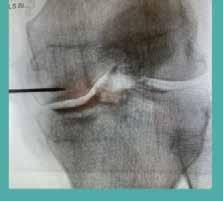

VETERINARY MEDICAL CENTER

Complete health care for your pet including diagnostics, reproductive services, orthopedics, general surgery, dentistry and internal medicine.

Advanced laparoscopic surgery and diagnostic procedures available including laparoscopic spays, gastropexy, minimally invasive abdominal explorations, comprehensive respiratory and gastrointestinal endoscopic procedures available.

Dr. Brad Hollstien

Dr. Sharon Klintworth

Dr. Meghan DeClue

805-461-3002

Hours 8am-5pm · Mon-Fri